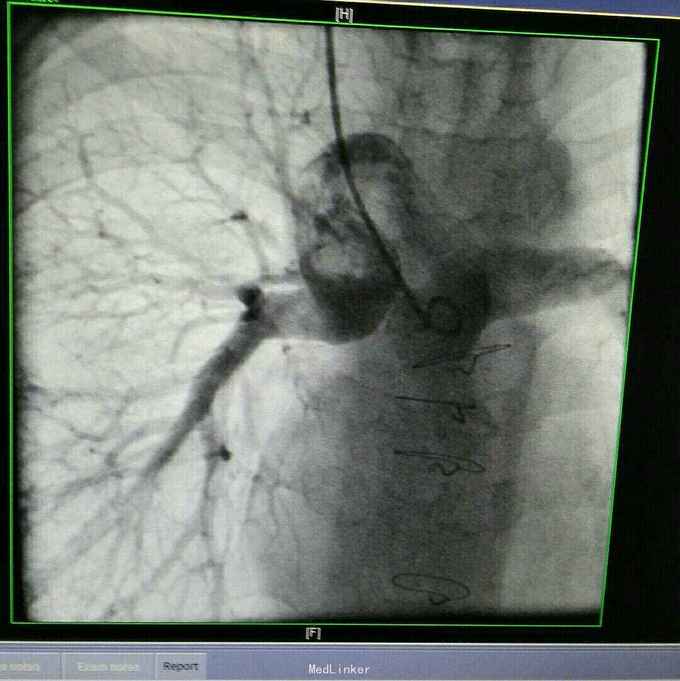

诊断 先天性心脏病 双向Glenn术后 单心室 大动脉转位 肺动脉瓣重度狭窄。 治疗 患者入院后完善各项术前检查及准备,在全麻体外循环下行全腔静脉肺动脉吻合术,手术过程顺利,术后胸腔引流液增大,带胸骨8天引流液减少拔出引流管,患者顺利出院。 手术过程患者取仰卧位,常规消毒辅单,胸骨正中入路,小心分流心脏,建立体外循环,取人工血管将下腔静脉连接与肺动脉,同时结扎主肺动脉,辅助循环后减量停机,常规关胸安反监护室。

先天性心脏病复杂畸形单心室大动脉转位 肺动脉瓣重度狭窄的手术疗难度很大,往往多选择右心废用增加肺血的手术方式,如双向Glenn手术先将上腔静脉与右肺动脉连接,让上腔静脉之血直接入肺增加肺血,二期再行全腔手术将下腔静脉连接与肺动脉这有进入右心的静脉血将直接入肺,增加肺血,提高血氧,改善患者缺氧,但该手术术后并发症也较多,同时必须肺动脉测压,如肺动脉压力 治 高,则为手术禁忌症。